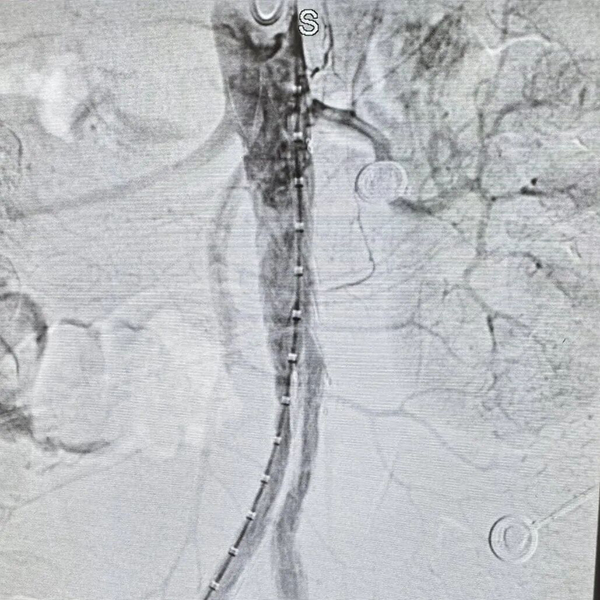

凌晨时分,导管室灯火通明。介入科喻四龙主任团队紧急上阵,在DSA下行腹主动脉造影+腹主动脉覆膜支架腔内隔绝术。随着支架精准释放,破裂口被成功封堵,孙大伯转危为安。

术前

术后